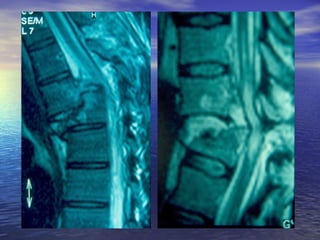

ΑΑππεειικκοοννιισσττιικκόόςς ΈΈλλεεγγχχοοςς

MM..RR..II..

ΕΕξξέέτταασσηη εεππιιλλοογγήήςς σσεε ππεερρίίππττωωσσηη

ννεευυρροολλοογγιικκήήςς σσηημμεειιοολλοογγίίααςς

ΑΑππεειικκοοννιισσττιικκόόςς ΈΈλλεεγγχχοοςς MM..RR..II.. ΕΕξξέέτταασσηη εεππιιλλοογγήήςς σσεε ππεερρίίππττωωσσηη ννεευυρροολλοογγιικκήήςς σσηημμεειιοολλοογγίίααςς